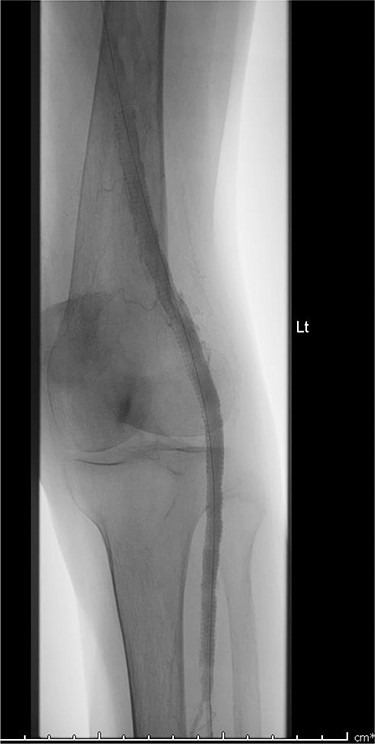

A 92-year-old female, independent from home, presented after multiple falls due to a four-month history of left foot drop. The foot drop had gradually worsened to the point that there was complete paralysis of ankle dorsiflexion and was associated with significant oedema of the foot. On examination, there was a large pulsatile mass in the popliteal fossa bilaterally. All peripheral pulses were palpable without any signs of ischemia. The most striking examination finding was complete paralysis of left ankle dorsiflexion with 0 out of 5 power. Ultrasound revealed that there were (Fig 1) bilateral popliteal artery aneurysms, which was larger on the left, causing displacement and impingement of the common peroneal nerve at the knee crease (Fig 2). Further computed tomography angiogram demonstrated an unruptured left PAA measuring 22 × 21 mm in maximal dimension over a distance of 24 mm (Fig 3). Intraluminal thrombus was also noted with 60% luminal stenosis. Distally, the arteries were heavily calcified with two-vessel runoff at the ankle. An emergency endovascular repair of the left PAA was performed by using 8 mm × 15 cm and 7 mm × 10 cm Gore Viabahn stents (Fig 4). The stents were deployed after a balloon-angioplasty and adequate decompression of the aneurysm was achieved. The postoperative period was uneventful, and patient’s pre-existing aspirin was continued. The leg and foot oedema improved rapidly over the subsequent few days. At follow-up in 12 weeks, the patient showed some return of motor function of the ankle and was walking with ankle splint. Her left leg remained well perfused with palpable pulses.

Computed topography angiogram image of left popliteal artery aneurysm, measuring 21 × 22 mm (AP × RL).